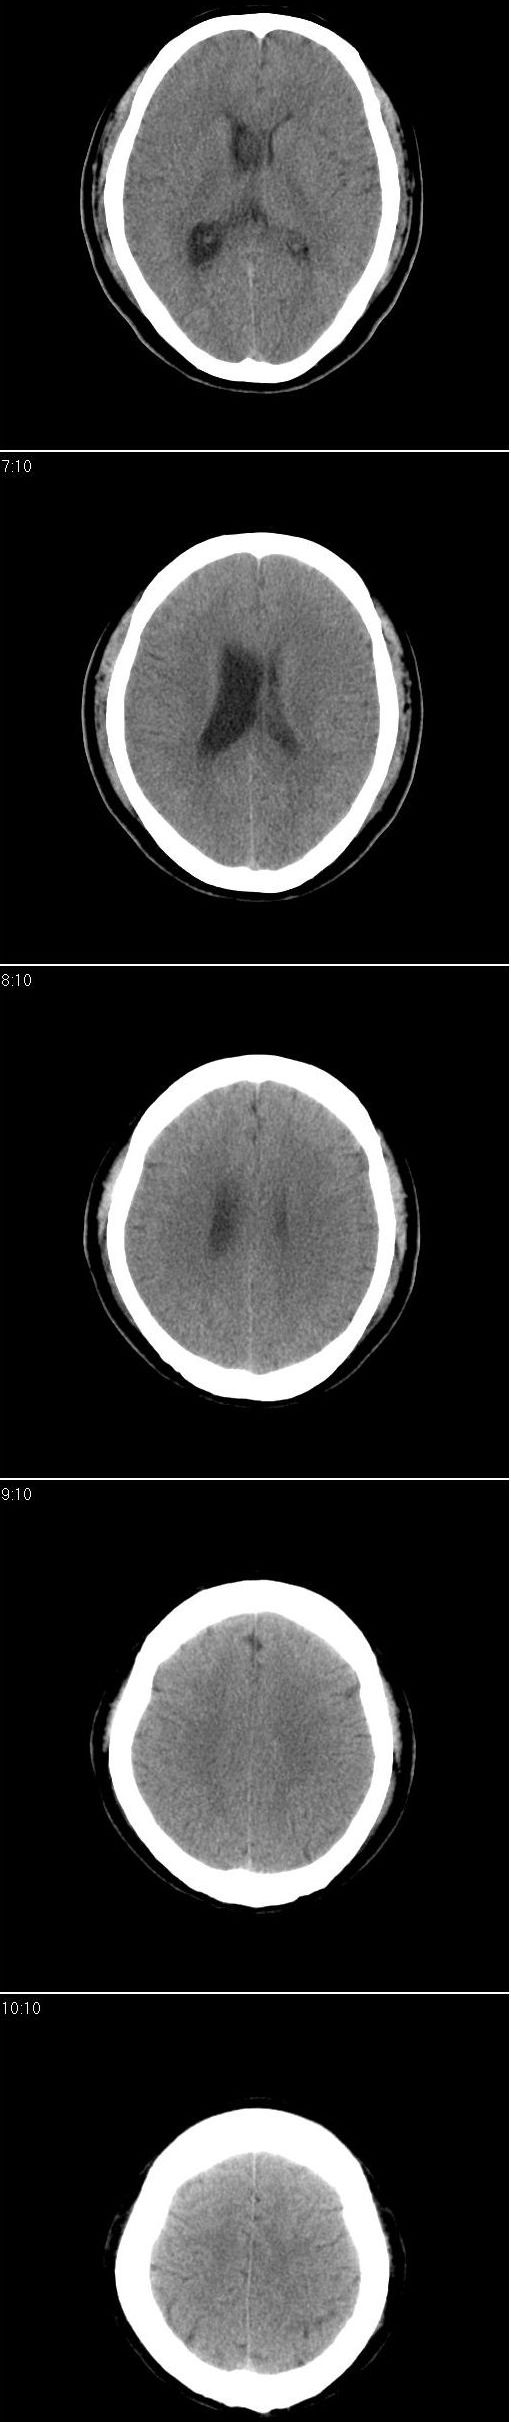

以下是引用形影不离在2008-5-3 16:55:00的发言:[br]考虑右侧侧脑室室间孔处胶样囊肿,并右侧侧脑室积水扩张。

以下是引用zhengfaming在2008-5-3 20:30:00的发言:[br]右侧侧脑室室间孔处似可见等密度结节影(图2),右侧侧脑室扩大,考虑占位.以室管膜瘤可能性大